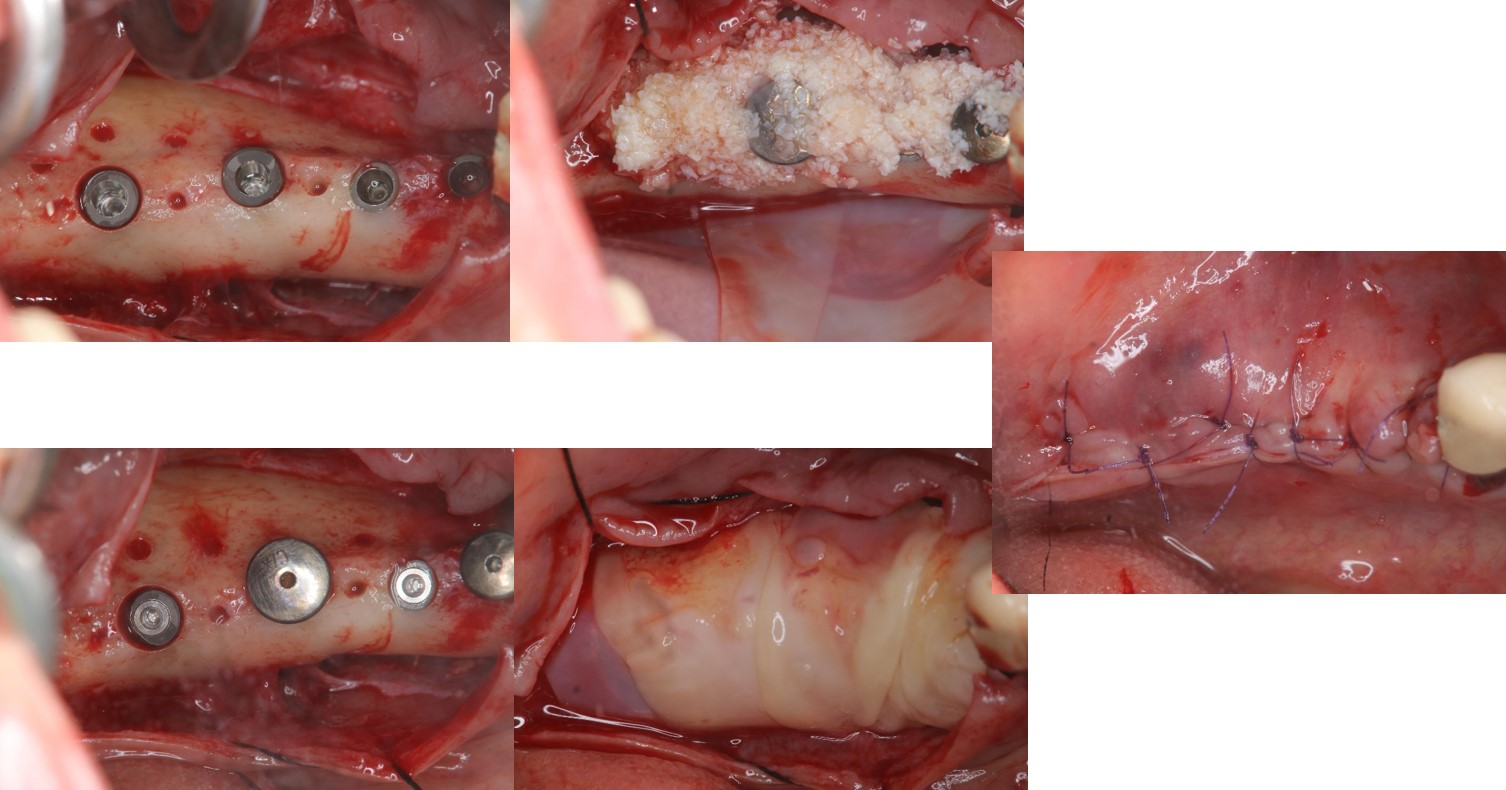

植體植入與補骨手術:#34-37

植體植入後X光確認:#34-37

植體二階手術與補皮手術:#34-37

▼檢查及分析完成後,醫生就開始了植體植入與補骨手術

▼植體植入後還要用X光確認,讓患者可以放心植牙有到位。

▼植體二階手術與補皮手術(果然照片比現場看的震撼,好在家人有打麻醉,換作是我可能光看就暈倒了吧!)